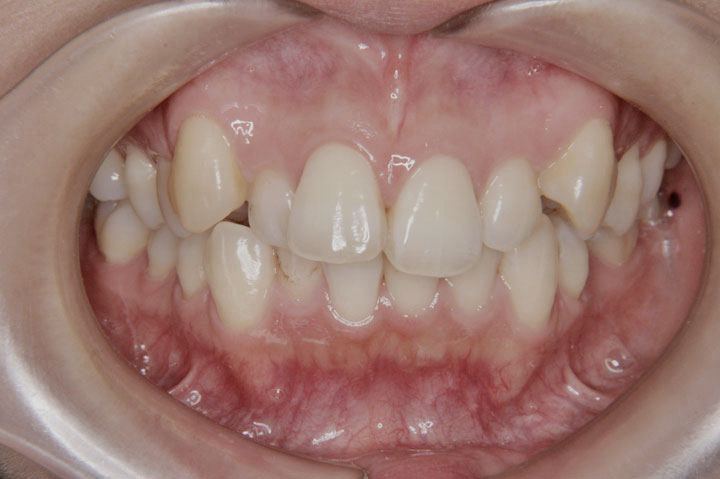

前歯の交叉咬合は、上顎の前歯の一部が、下顎の前歯のよりも内側に入っている状態です。かみ合わせが逆転することで、種々の不利益を引き起こします。通常は、叢生と複合することが多い不正咬合です。お子様の場合、低学年(7~9歳)であっても、交叉咬合と判断される場合は、受診をお勧めいたします。 その時期であれば、比較的良好な治療結果となることが多いと思います。成人の方の治療も可能ですが、負担のかかった歯肉などは、回復できない場合もあります。

症例(40)

【混合歯列 抜歯】